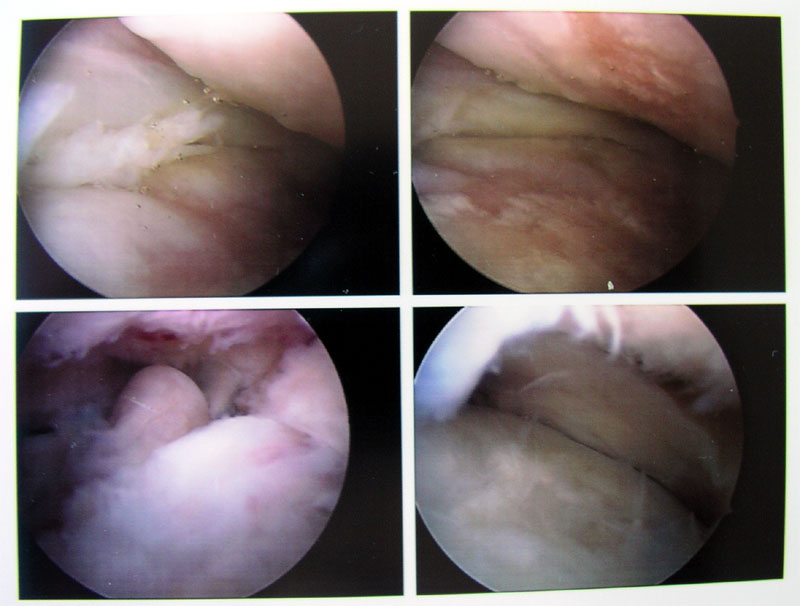

9. August 2005, 10.15 Uhr: Ansichten eines Knies

Knie von innen - klicken für grössere FassungNun sieht man dieses vermaledeite Gelenk endlich mal von innen! Ich erkenne zwar nichts - aber falls jemand mehr aus diesen Strukturen rauslesen kann, bin ich dankbar für Informationen... Bitte auf das Foto klicken für eine grössere Fassung! (Auf dem Bild rechts oben, wie mir inzwischen erklärt wurde, ist unten das Tibiaplateau sichtbar, oben die Gelenkfläche des Oberschenkels, hinten der Meniskus - die unregelmässige Fläche bedeutet, dass ich eine für mein Alter massiv fortgeschrittene Arthrose habe. Im Bild links unten ist ein Teil eines nachträglich entfernten Knochenfragmentes im Hintergrund sichtbar.)